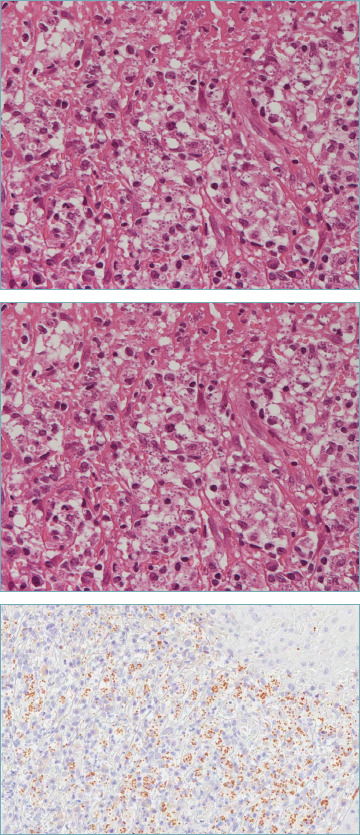

Leishmaniasis is an infectious disease caused by a protozoon of the genus Leishmania. It can manifest as cutaneous, mucosal, localized lymphadenitis forms or it can result as multiorgan involvement. In this article we present the case of a 59-year-old male with a polypoid mass attached to the septum at the right nasal cavity and symptoms as nasal congestion, hyposmia and anterior rhinorrhea. Histological sections of the mass showed oval-shaped inclusions in the cytoplasm of histiocytes suspicious for Leishmania amastigotes. The diagnosis was confirmed by detection of Leishmania complex DNA with polymerase chain reaction (PCR).